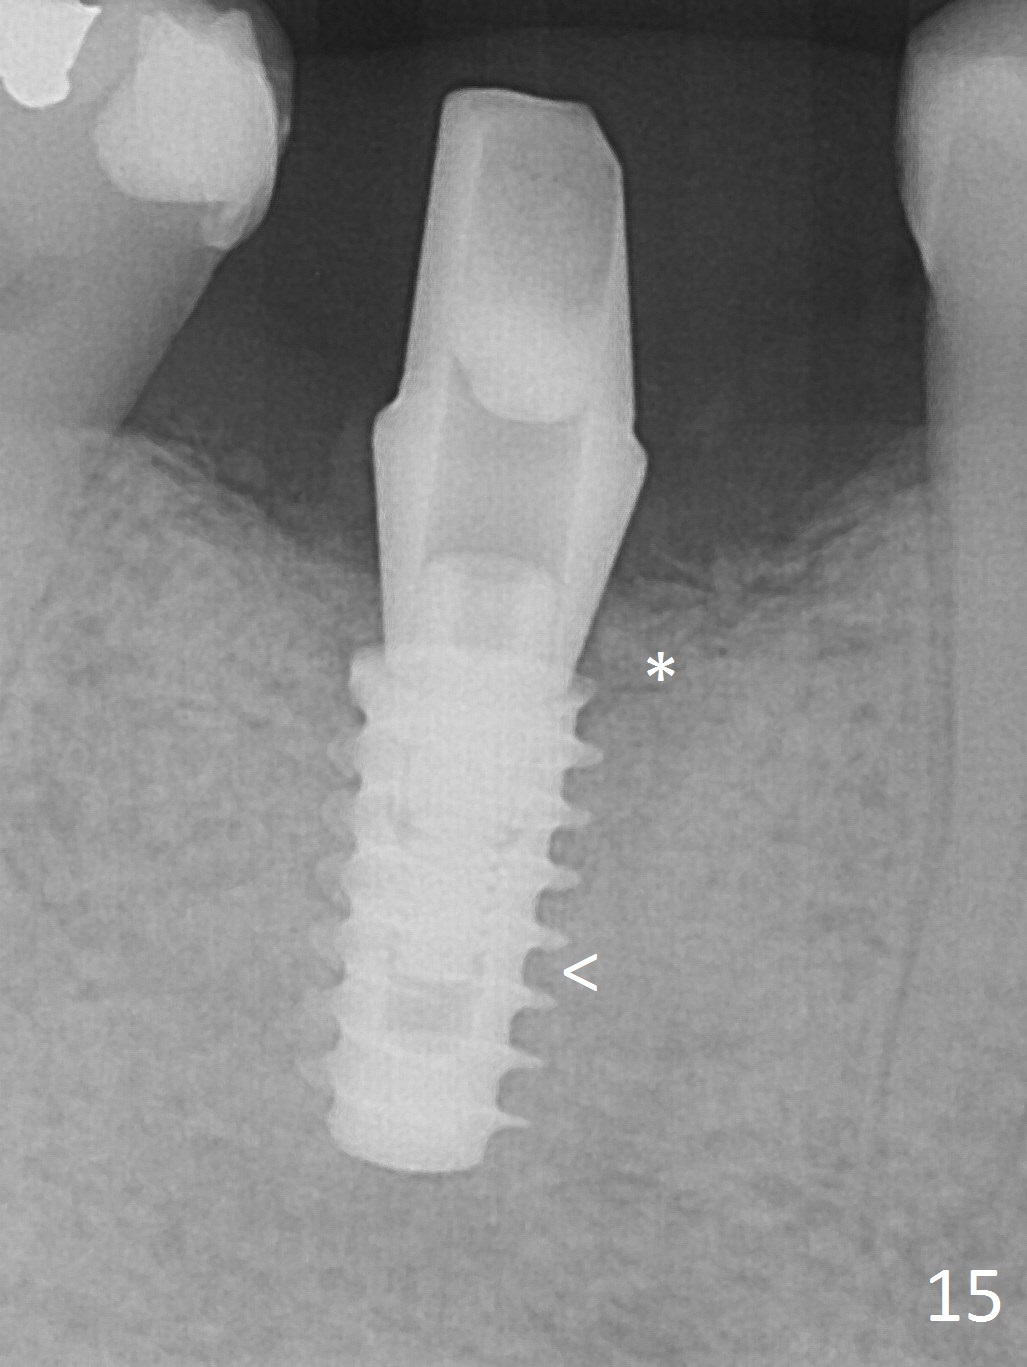

Implant threads appear to have been covered by bone coronally (Fig.15 *) and apically (<) 5 months postop. The provisional remains in place (Fig.16), although dislodged twice and replaced by the patient. The gingiva around the provisional and abutment is healthy (Fig.17 after packing with gingival retraction cord for impression).